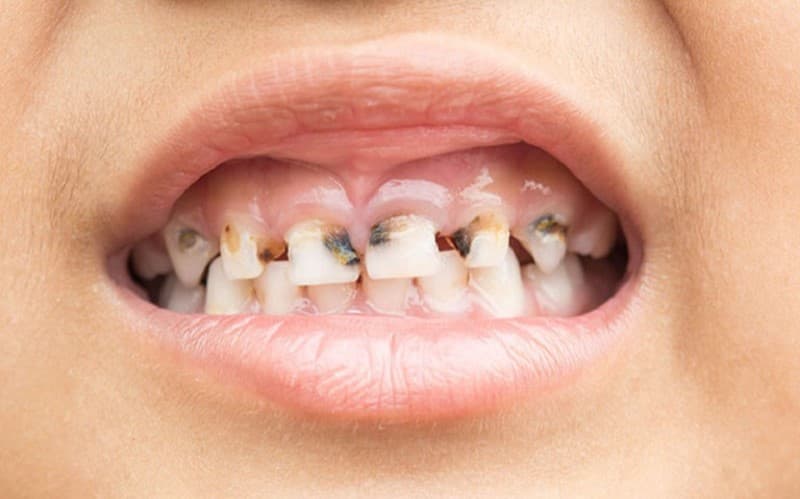

1. Những dấu hiệu của tình trạng sâu răng cửa

Sâu răng cửa thường khá dễ nhận thấy bằng mắt thường

Răng cửa ở vị trí dễ nhìn thấy, đặc biệt nếu như sâu xuất hiện ở phía ngoài. Dưới đây là một số biểu hiện thường gặp của sâu răng cửa:

– Vết đen trên răng: Dù sâu răng cửa thường không gây ra các dấu vết rõ ràng trên bề mặt răng nhưng chúng ta vẫn có thể nhận ra những thay đổi. Các dấu vết nhỏ hoặc đốm đen có thể xuất hiện gần viền nướu hoặc trên bề mặt răng.

– Lỗ sâu: Trong một số trường hợp, bạn có thể nhìn thấy hoặc cảm thấy một lỗ nhỏ trên bề mặt của răng. Đây có thể là dấu hiệu của sâu răng cửa đã phát triển